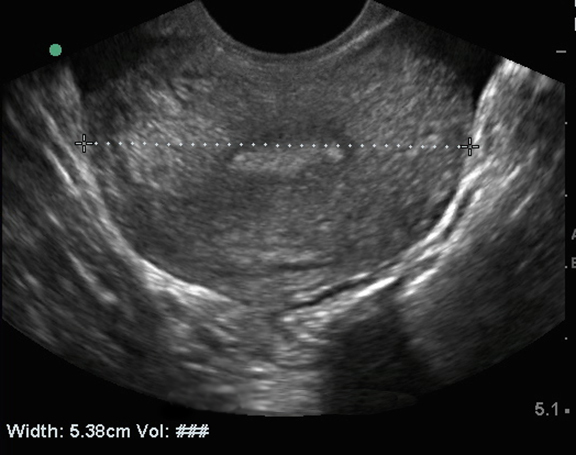

Pélvica intravaginal del útero: Imagen transversal 3

Mediciones transversales del útero